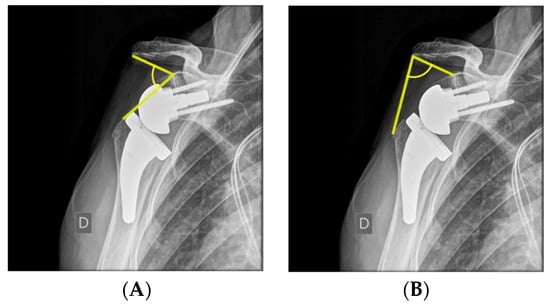

3. Scapular Posture